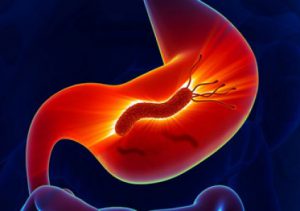

سرطان معده چیست؟ + علت، علائم و راه های درمان

سرطان معده چیست؟ + علت و راه های درمان آن

علت سرطان معده چیست؟ + علائم و راه های درمان